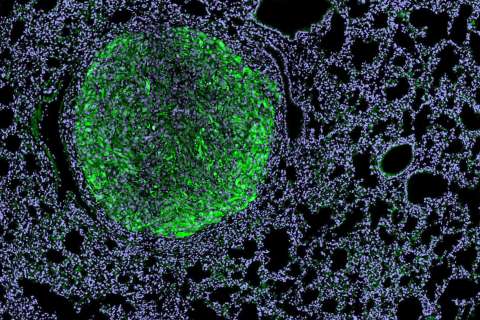

Scientific Interests

Dr. Arnold Chin's Laboratory is dedicated to improving the lives of patients with urologic malignancies. Much of their initial studies have focused on understanding the molecular pathways that program the tumor infiltrating lymphocytes in bladder and prostate cancer, which they have shown can influence tumor growth, ability to metastasize and response to immune-based therapies. More recently, they began studying the characteristics and drivers of bladder cancer stem cells.

Chin's laboratory currently studies two main areas:

- They have identified an alternatively spliced form of a transcription factor, FOXP3, that activates and makes bladder cancer stem cells more aggressive. They will exploit this observation by understanding its basic biology and develop novel inhibitors of FOXP3.

- They are characterizing the tumor population in micrometastatic lymph nodes, which they hypothesize is enriched in a cancer stem cell population. Identifying this population will improve pathologic staging as well provide therapeutic insight into inhibiting the process of metastases.